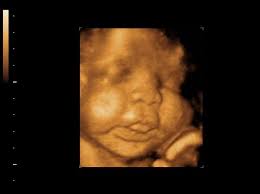

Of the many defects 3D 4D ultrasound has been useful in evaluating the skeletal and cardiovascular systems in fetuses with this condition. But keeping tabs on your babys growth can be a good thing and knowledge is power. By combining the results of the two parts of the test it is possible to identify if a pregnant woman is at increased risk of having a baby with Down syndrome.

A normal heart rate for a baby ranges from 120 to 160 beats per minute. By itself the test does not tell. These include increased nuchal translucency short femurs and abnormalities of the heart bowel and kidneys.